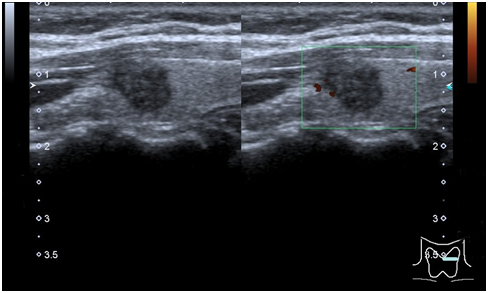

We report a case of PTC discovered by E. A 54years old female with a studied thyroid nodule during 5years, was performed US and E. The nodule was described as circumscribed, markedly hypoechoic, with no vessels, in thyroid left lobe. With a diameter of 9mm, stable during the time. E shown an inner area of stiffness (3mm size) and an outer area softer. Thyroid homogeneous echogenicity, without evidence of another nodule. We performed FNA E-guided of stiffness area. The cytology reported compact clusters of follicular cells with moderate anisokaryosis, empty nuclei and papillary branches, with microcalcification, that indicated suspicion of papillary carcinoma (Bethesda V). At surgery cancer had spread to local lymph nodes. The patient was undergone completion thyroidectomy and received radioactive iodine treatment (Figure 1) (Figure 2).

Figure 2 Elastogram (left) and gray scale (right) of thyroid nodule. Scale E represents stiffness areas with color blue, and softer with green and red. This E shows a stiffness inner area (with a 4.39 SR) with a softer outer area.

There are two types of E: semi-quantitative (strain E) and quantitative (shear-wave E). We use strain E. Strain E detects the local deformation under slight pressure and displays it as a relative value in comparison to the strain values of the different tissues within the region of interest. To acquire the elastographic images, compression is continuously applied by a transducer and followed by decompression. The elastic image is superimposed on the B-mode image, and tissue stiffness is displayed in a continuum of colors from red (soft tissue) to blue (hard tissue). We use Ueno scale. A score of 1 defined elasticity that is entirely soft in the nodule, 2 as mostly soft in the nodule, 3 as peripherally soft, 4 as entirely hard in the nodule, and 5 as hard in the area under consideration as well as the entire nodule. We chose particularly the valley area or the ascending part of one wave (compression). Two regions of interest (ROIs) are drawn over the target region and the adjacent reference region, respectively. Then, a strain ratio (SR) is automatically calculated, with a maximum value considered normal up to 2.45. The likelihood of malignancy increases with an increase in the strain ratio.4 There are limiting factors that can affect the results of elastography, including nodule characteristics (calcifications and cystic components), the experience of the operator, and motion artifacts such as carotid artery pulsation. However, E optimizes the US imaging. In our case, the FNA of stiff area was E guided. The E is a promising technique to guided FNA and predict the preoperative malignancy risk.